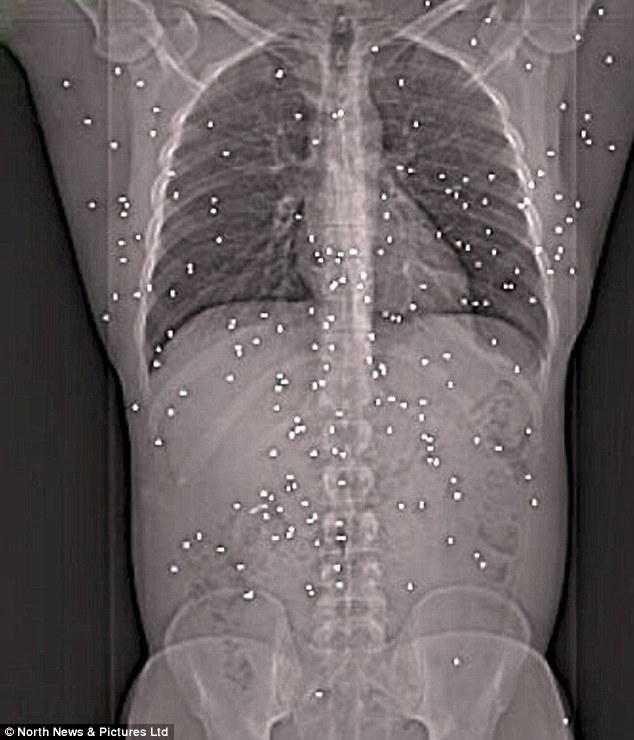

Peppered by 150 shotgun pellets: Victim survives but will die 25 years ...

Shotgun. click pic to view larger image